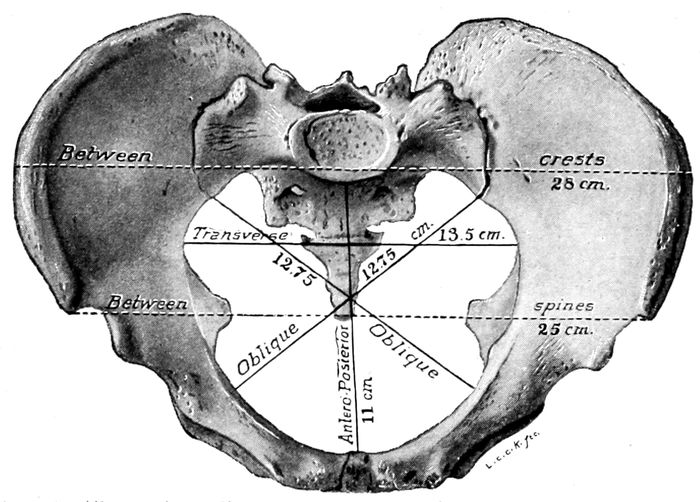

Fig. 1.—The normal female pelvis. (Eden.) The lines ab and cd divide the pelvis into the right and left anterior and the right and left posterior quadrants. ab indicates the anteroposterior diameter of the brim, cd shows the transverse diameter while gh and ef represent, respectively, the right and left oblique diameters.

19The brim or inlet has four important diameters to be

remembered; important because the hard, round head

of the child must pass through them by accommodating

its diameters as favorably as possible to those of this

opening. These diameters are named respectively the

anteroposterior or conjugate diameter, the transverse,

and the right and left oblique diameters. The two

oblique diameters attain their greatest importance when

the pelvis is irregularly distorted, but the others are

essential in every case where labor impends. It is to

secure an estimate of these latter diameters that the

bony prominences are measured. This upper opening